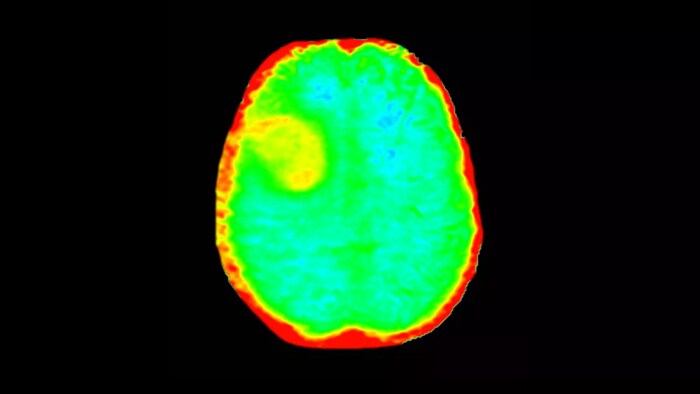

3D APT